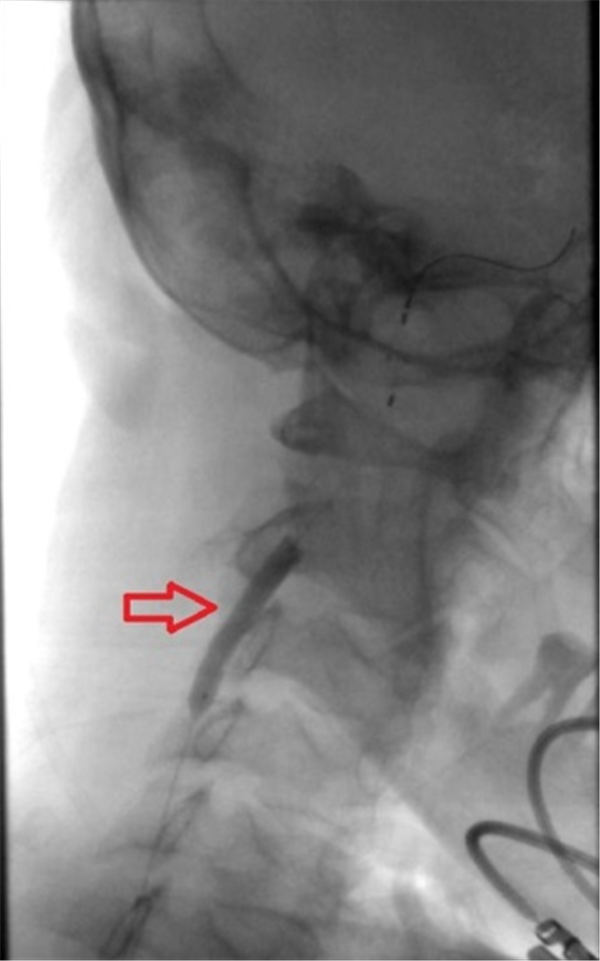

球囊完全扩张之后,动脉狭窄消失(上图红色箭头之间)。